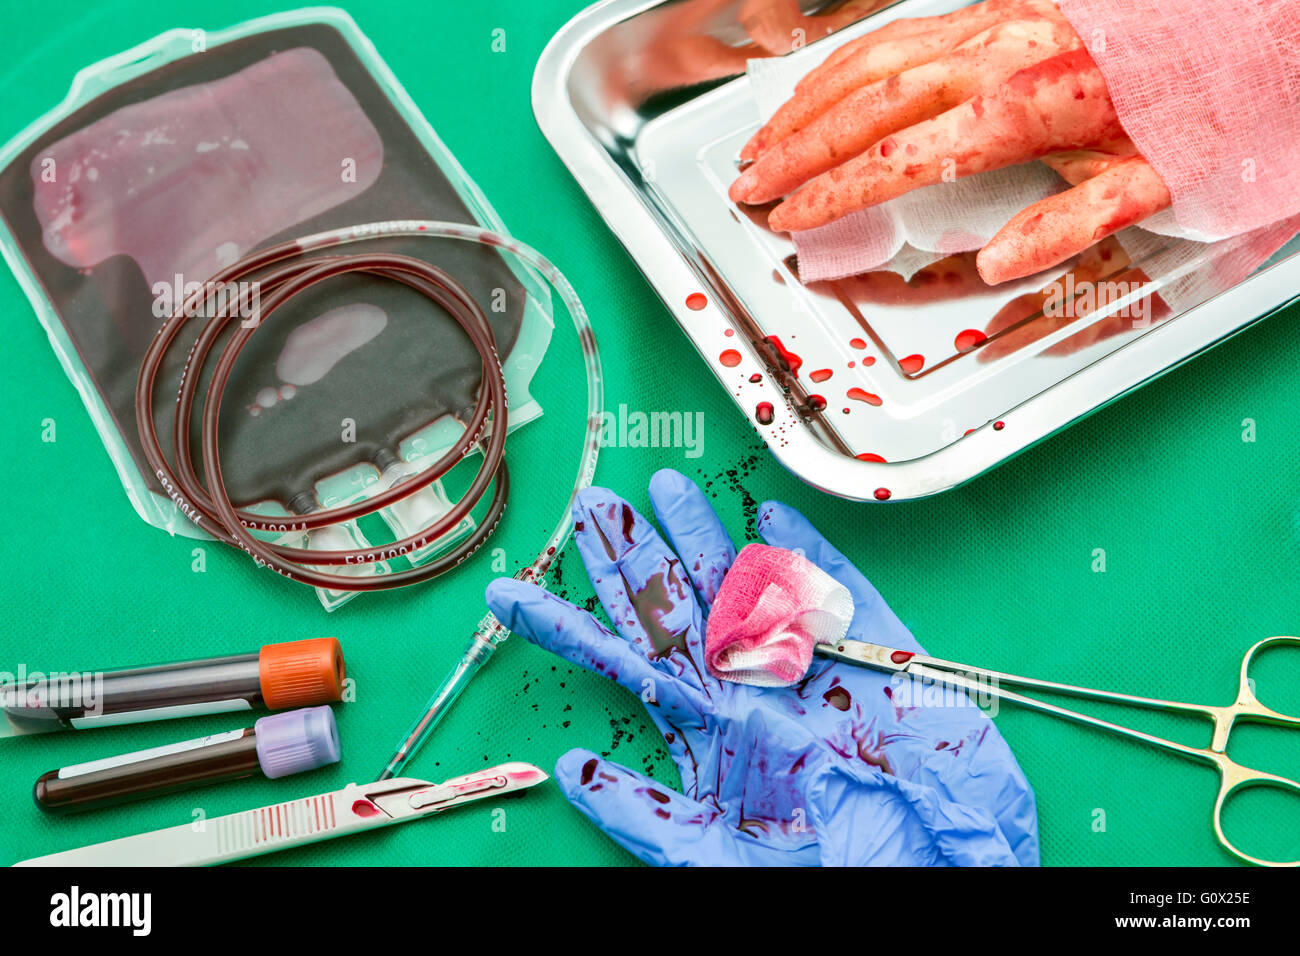

RFG0X245–Einheit der Konzentration der roten Blutkörperchen, blutstillende Kocher Pinzette, Transplantation des oberen Extremität in einem OP-Raum

RFG0X21P–Einheit von Konzentrat roter Blutkörperchen, Transplantation des oberen Extremität in einem OP-Raum

RFG0X25T–Einheit von Konzentrat roter Blutkörperchen, Transplantation des oberen Extremität in einem OP-Raum

RFG0X24W–Einheit der Konzentration der roten Blutkörperchen, blutstillende Kocher Pinzette, Transplantation des oberen Extremität in einem OP-Raum